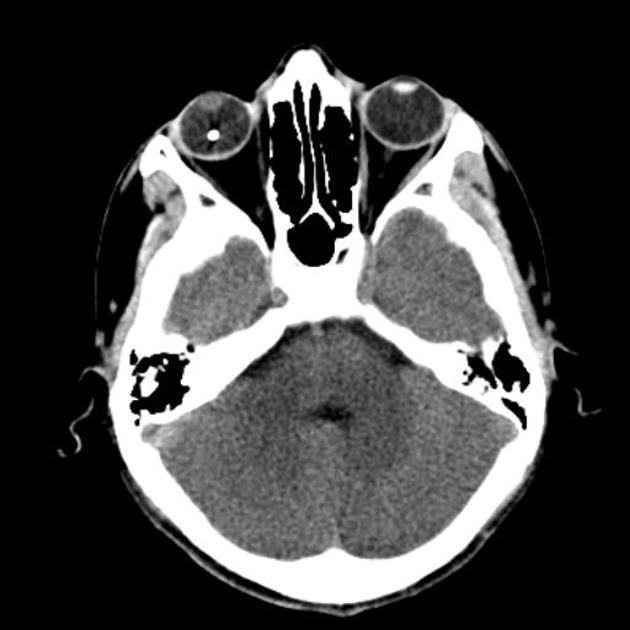

Head CT shows a bleed in the eye (choroidal hemorrhage). radiologist radiology Is Ct Scan Harmful For Eyes Ct scans themselves usually don’t cause side effects. For example, there’s a higher chance of allergic reactions to the dyes, and they’re also not good for your kidneys. The most common ct scan side effect is a specific form of allergic reaction to the contrast dye. However, there are a few risks associated with using contrast dyes. These side effects. Is Ct Scan Harmful For Eyes.